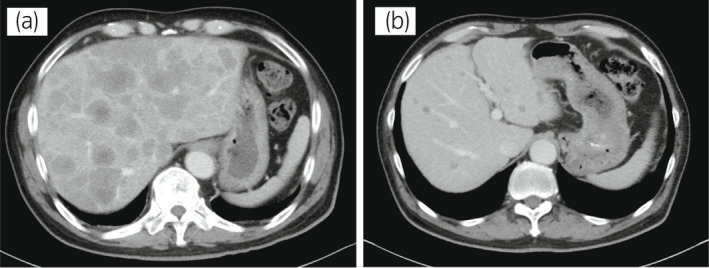

一名 78 歲男性被診斷為 cT3bN0M0,GS 為 4 + 4 =⟩8,PSA 水平為 15.2 ng/ml 7 年前,并接受了前列腺切除術(shù)。 六個(gè)月后,PSA 升高并開始雄激素剝奪治療。 兩年后,開始使用比卡魯胺治療 CRPC。 服用比卡魯胺五個(gè)月后,患者被轉(zhuǎn)診至佳學(xué)基因檢測合作醫(yī)院。 在接下來的 2 年內(nèi),依次給予恩雜魯胺、多西他賽和卡巴他賽。 多西他賽前的 MRI 顯示髂骨轉(zhuǎn)移,多西他賽和卡巴他賽治療后消失。 開始使用卡巴他賽后 6 個(gè)月,他出現(xiàn)雙側(cè)盆腔淋巴結(jié)腫大,并在膀胱后壁發(fā)現(xiàn)轉(zhuǎn)移性腫瘤。 在進(jìn)行經(jīng)尿道切除術(shù) (TUR) 期間,從膀胱中的轉(zhuǎn)移性腫瘤獲得組織樣本。 病理檢查顯示嗜鉻粒蛋白 A 陽性,NSE 水平升高,因此我們診斷為 NEPC。 卡鉑和依托泊苷聯(lián)合治療縮小了腫瘤。 此后,在 24 個(gè)月內(nèi)進(jìn)行了 17 個(gè)療程,疾病得到控制。 由于神經(jīng)病變和疲勞而停止化療。 隨后,患者出現(xiàn)盆腔淋巴結(jié)轉(zhuǎn)移進(jìn)展(圖 4a)。 通過血液檢測 (BRCAnalysis®?) 進(jìn)行的基因檢測對 BRCA 突變呈陰性。 使用 TUR 時(shí)收集的膀胱轉(zhuǎn)移組織進(jìn)行腫瘤正確用藥850基因檢測。 結(jié)果顯示,該患者的體細(xì)胞 BRCA2 突變呈陽性。 在奧拉帕尼給藥后的 3 個(gè)月內(nèi),淋巴結(jié)從 21.0mm 縮小到 7.5mm(圖 4b)。 PSA 從 1.42 下降到 0.07 ng/ml,NSE 從 22.3 下降到 11.8 ng/ml。

圖 4:病例 2:奧拉帕尼治療前和治療后 3 個(gè)月的盆腔淋巴結(jié) CT 圖像。 (a) 治療前和 (b) 奧拉帕尼治療后 3 個(gè)月。 黃色箭頭顯示轉(zhuǎn)移淋巴結(jié)。